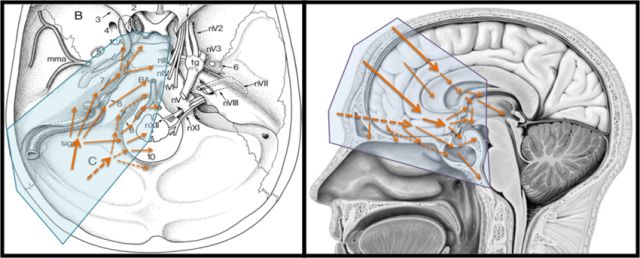

Samii临床神经解剖实验室

颅颈交界区显微解剖

小脑幕切迹显微解剖

前床突区域显微解剖

眶尖显微解剖

白质纤维解剖

内镜解剖